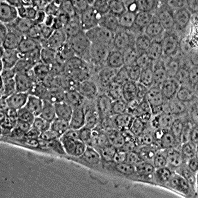

Capan-2

Морфология:

полигональная

Способ культивирования:

монослойный